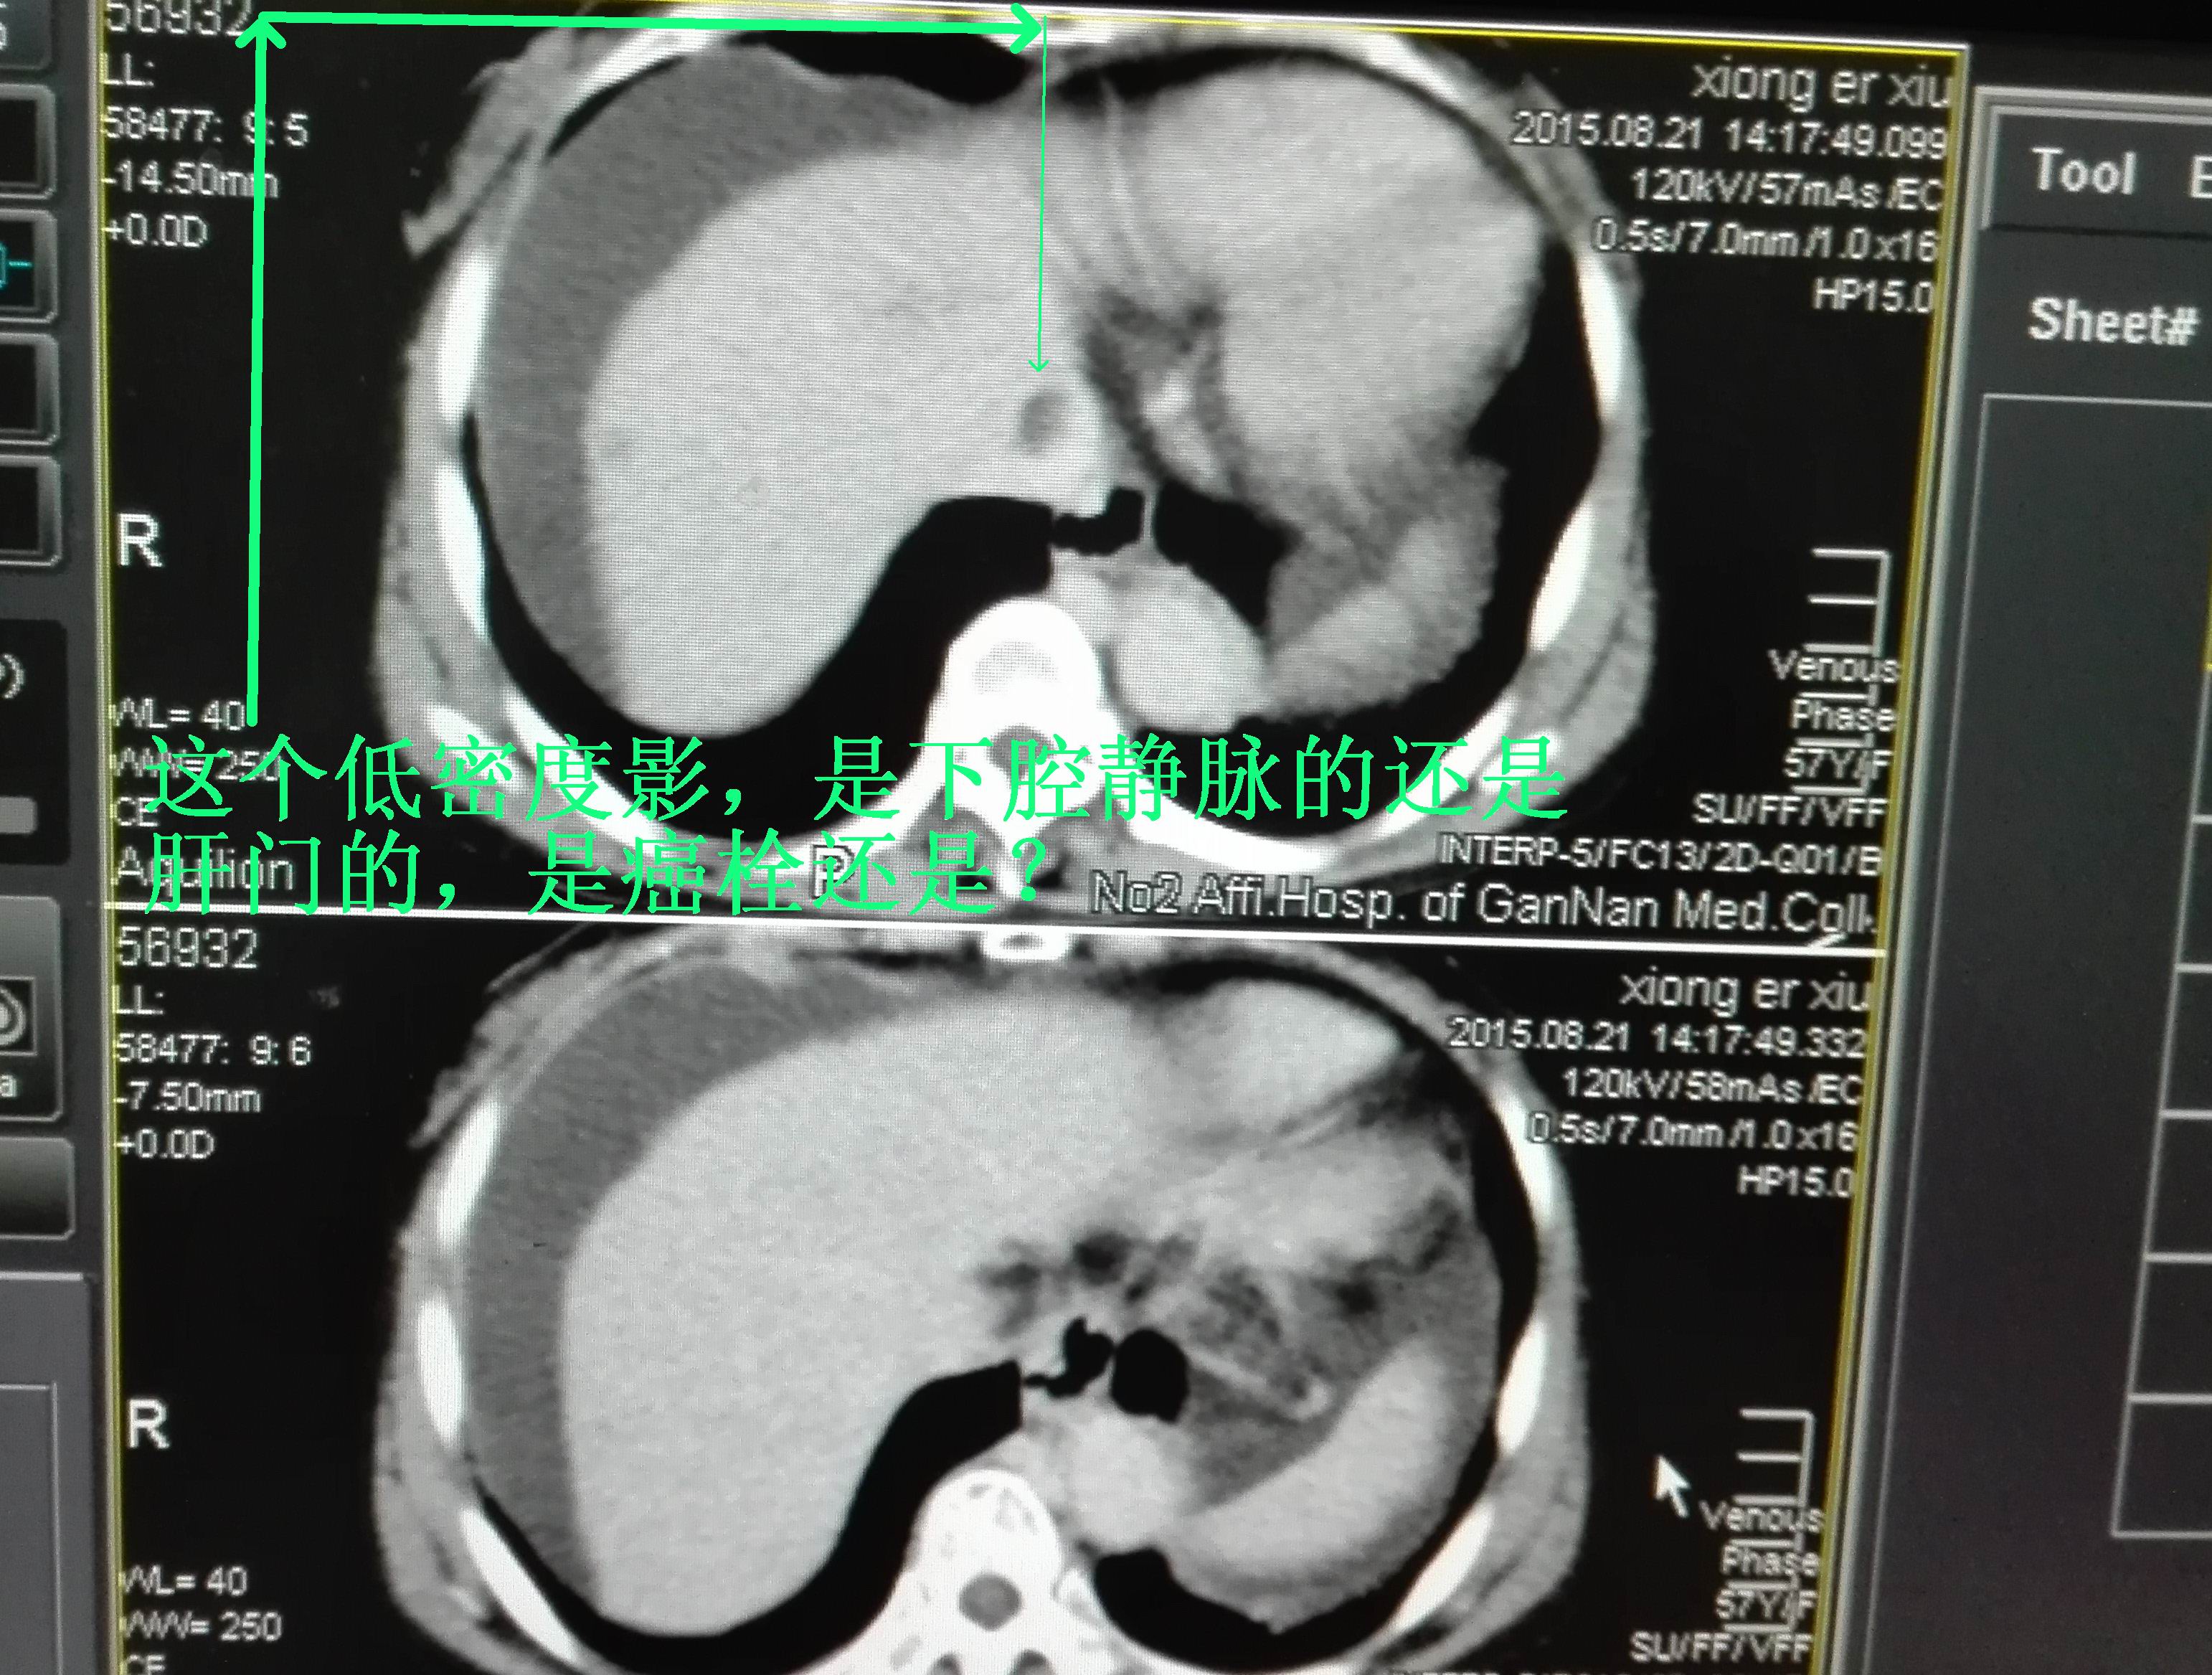

1)考虑肝左叶内侧段肝癌并门静脉瘤栓形成。2)肝右叶后下段近肝边缘占位;多为血管瘤。3)肝硬化,脾大,腹水。4)肝病性胆囊。5)膈下段下腔静脉旁局限性脂肪积聚。

感觉像血管瘤,但下腔静脉区域的低密度影不好解释,是癌栓的话,肝右叶病灶要考虑转移灶?胆囊看看有没有问题,感觉壁厚,胆囊壁做增强,有强化吗?谢谢

肝脏体积缩小,脾大、腹水,肝左叶见结节,内见低密度坏死,增强呈快进快出,肝右叶后段近包膜下结节,呈渐进行强化,门静脉见缺损,膈下及下腔静脉旁似见脂肪密度,胆囊体积小,壁较厚,考虑:肝硬化,肝左叶肝癌并门静脉癌栓形成,肝右叶占位,考虑血管瘤可能性大。膈下及下腔静脉旁脂肪堆积?胆囊炎?